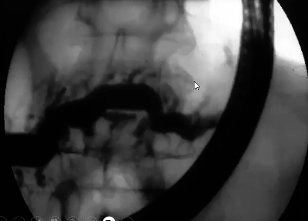

noninvasive alternative to ERCP for imaging pancreatic duct

MRCP

highly sens test for CP (radiographic)

ERCP